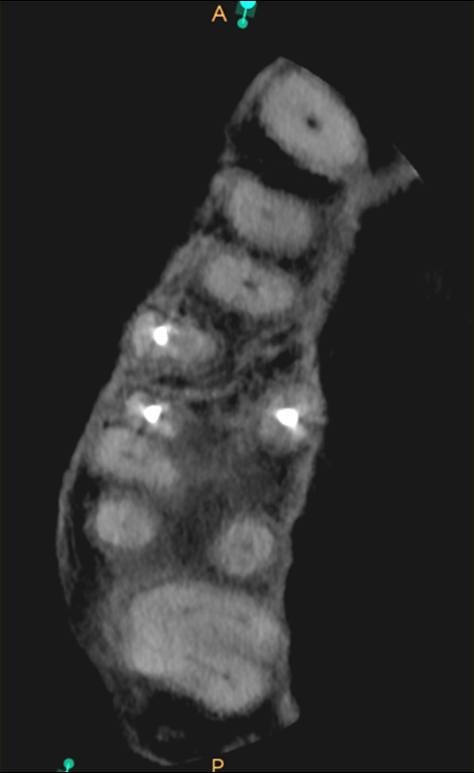

Es necesario resaltar que diversos estudios han demostrado que, en ocasiones, el MB2 puede ser localizado clínicamente, incluso si no es visible en la imagen de la tomografía7. La TCHC brinda información anatómica adicional que puede mejorar la detección de conductos en la raíz mesiovestibular de los molares superiores, así como prevenir el desgaste excesivo de estructura dentaria o errores iatrogénicos como consecuencia de la búsqueda de conductos en localizaciones erradas o inexistentes. El valor de la tomografía no solo está en mostrar el conducto de forma directa, sino en toda la información anatómica que aporta para localizarlo de forma exitosa (Fig. 2).

Fig 2. Imagen axial del diente 16 que muestra un conducto obturado en la raíz mesiovestibular.

Su posición anatómica sugiere la presencia del MB2